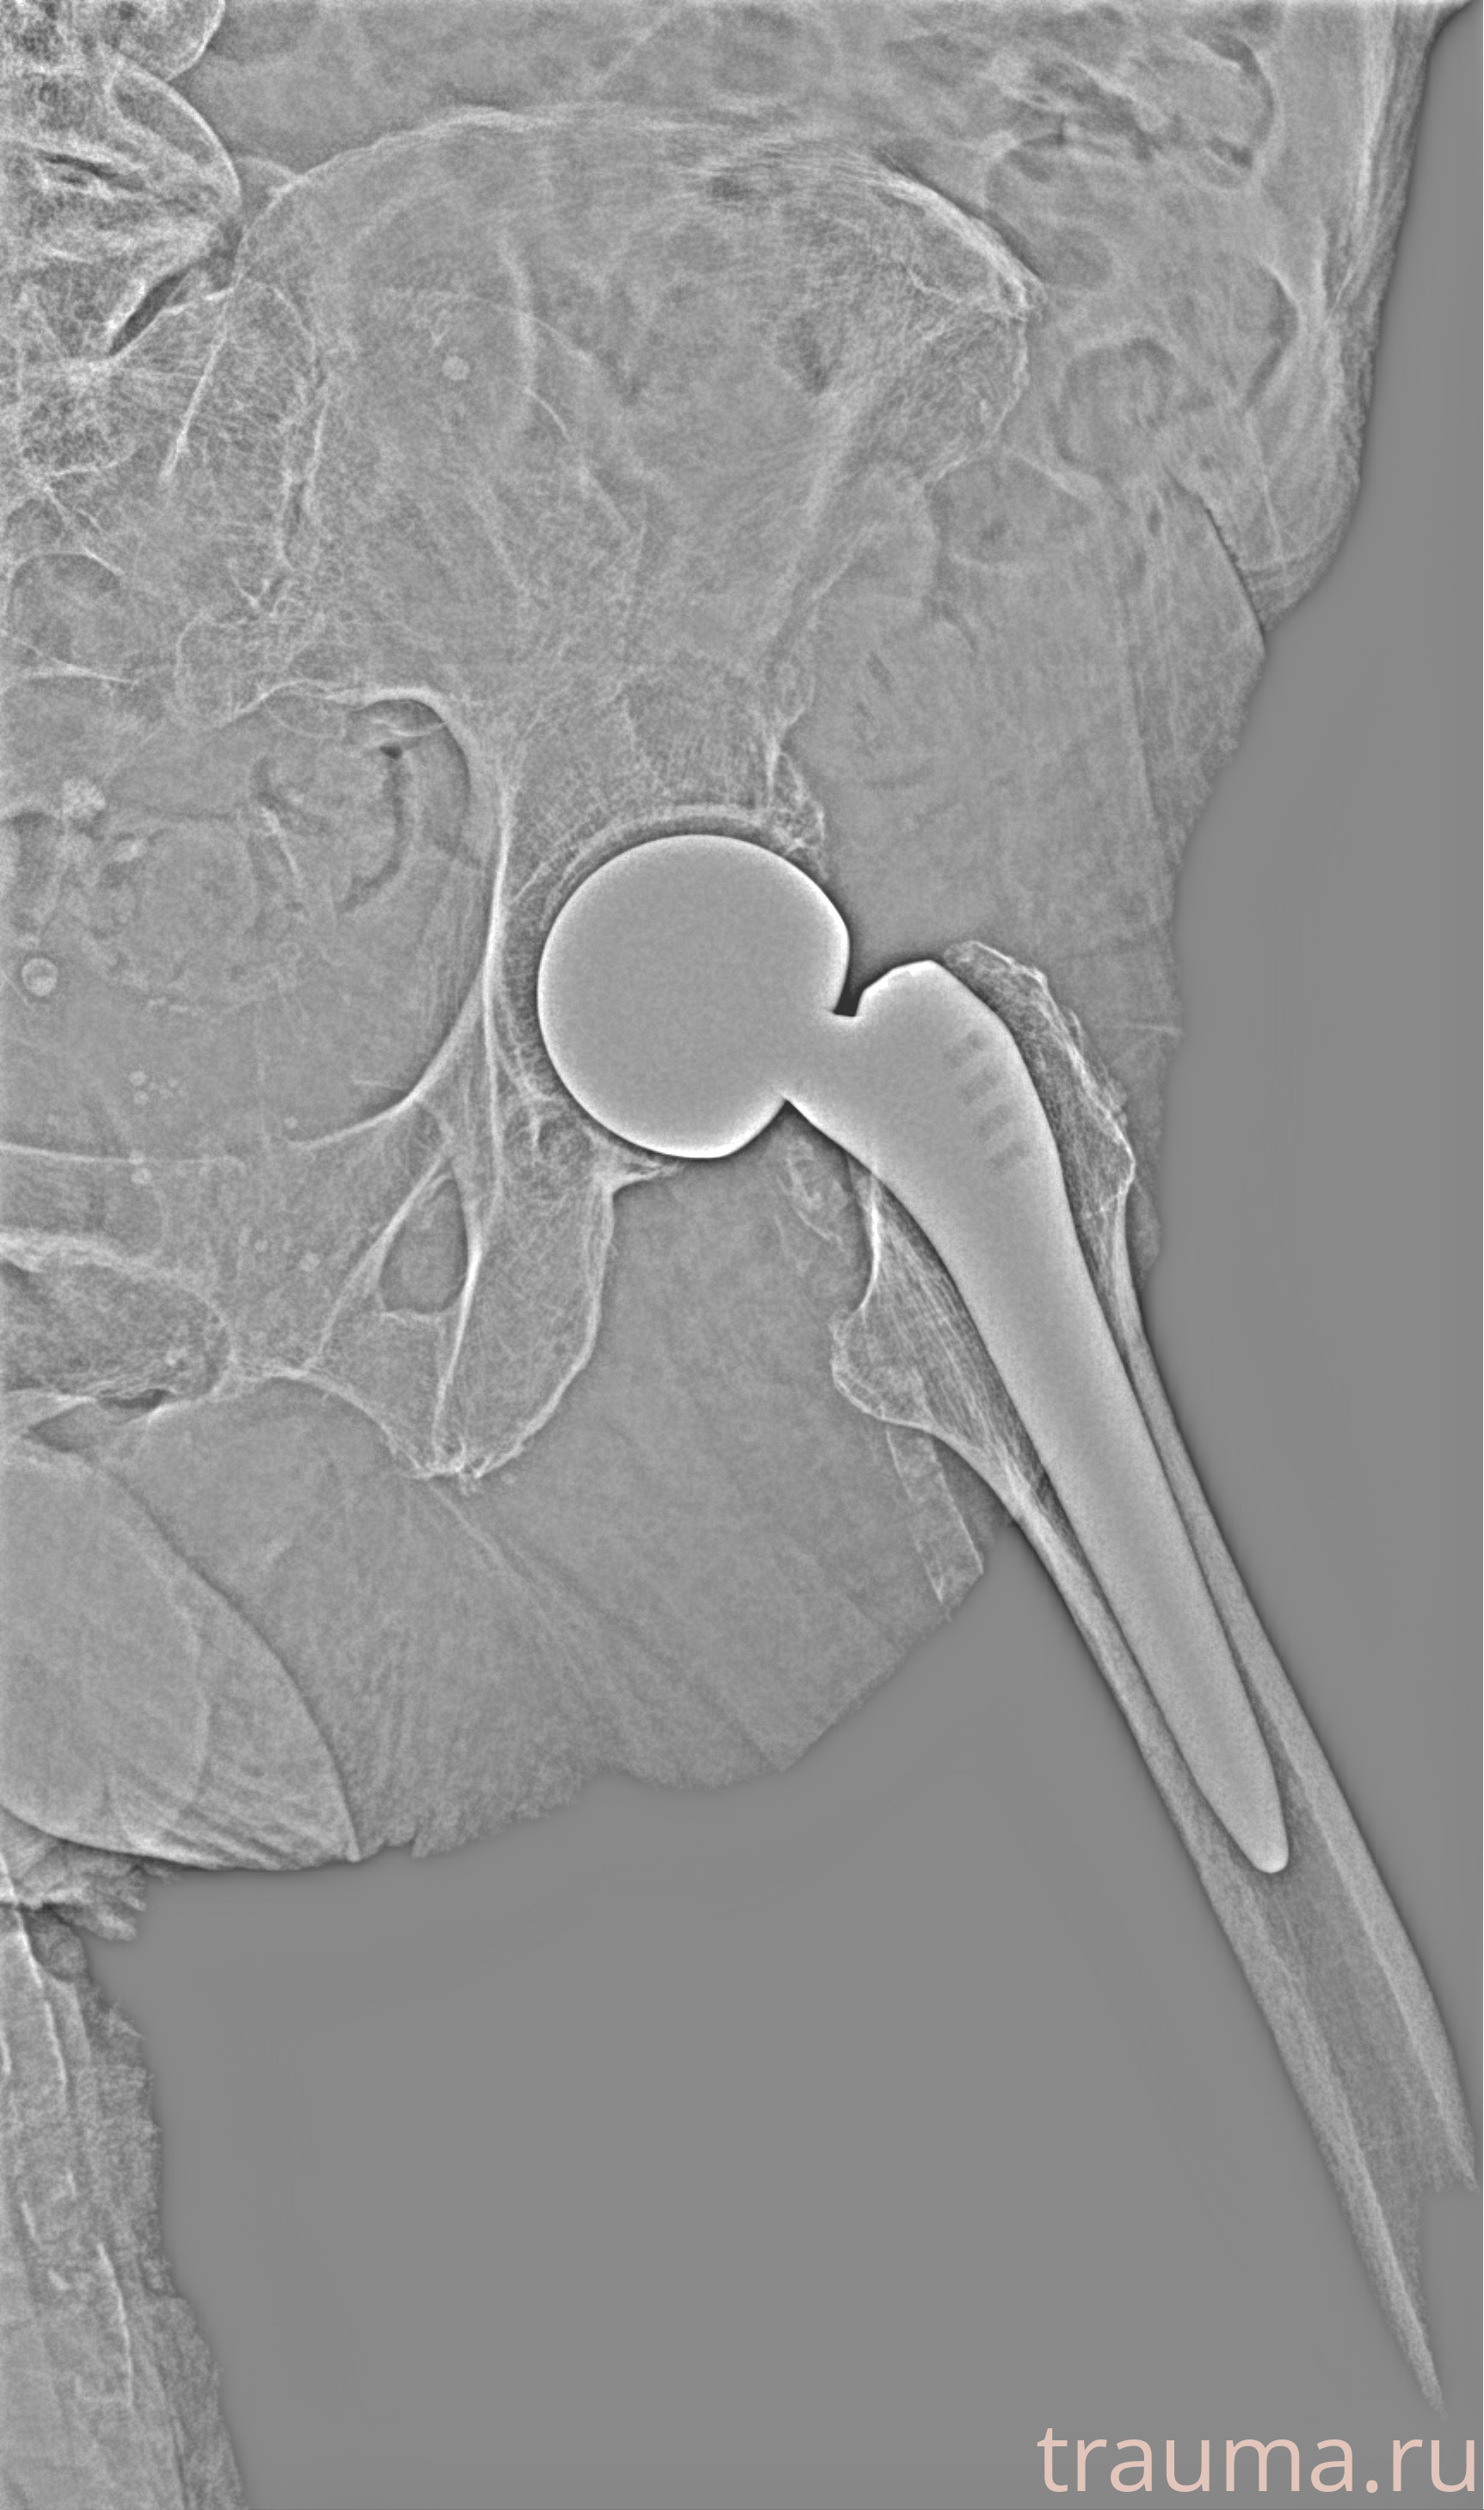

Рентген на дому: по вашему адресу приезжает врач-рентгенолог, травматолог-ортопед с мобильным рентгеновским аппаратом, проводит диагностику травмы или заболевания, делает необходимые рентгенограммы, дает рекомендации по дальнейшему лечению. Получить качественные снимки в домашних условиях возможно благодаря уникальной методике, разработанной МосРентген Центром для института  Склифосовского